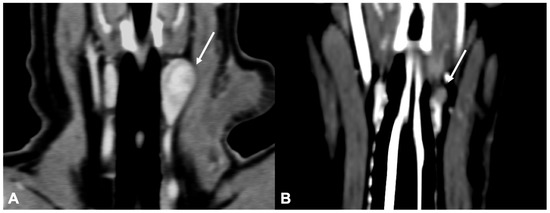

Only 1 of the 21 dogs included presented with primary hyperparathyroidism caused by an ectopic parathyroid adenocarcinoma. The nodule in this case was located in the cranial mediastinum, between the cranial mediastinal lymph nodes and the brachiocephalic trunk, rounded, and with heterogeneous contrast enhancement (Figure 5). Despite the localization, the presence of a single abnormal cranial mediastinal lymph node was considered unlikely and the presumptive diagnosis of ectopic parathyroid tissue was made based on the CT (than confirmed by histological examination).

Figure 5.

CT appearance of an ectopic parathyroid gland adenocarcinoma. Post-contrast transverse (A), sagittal (B), and dorsal (C) CT reconstruction images of a dog with diagnosed parathyroid gland adenocarcinoma (arrow) at the level of the cranial mediastinum. † = cranial vena cava; * = left subclavian artery; ** = brachiocephalic trunk. Note the cranial mediastinal lymph nodes (within the circle).